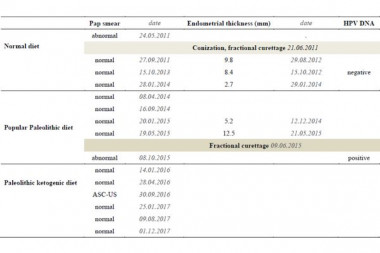

Complete Cessation of Recurrent Cervical Intraepithelial Neoplasia (CIN) by the Paleolithic Ketogenic Diet: A Case Report.